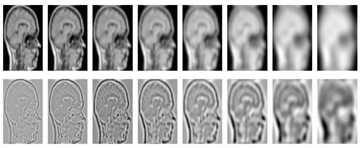

- Gaussian Scale-Space representation: this concept [93,94,95,96] makes it possible to manage image structures at different scales by generally smoothing. This representation is obtained by solving a linear diffusion equation. Its transparent and natural way of handling scales at the data level makes this concept popular. However, it is sensitive to signal noise since smoothing is applied without an average filter. In addition, parasitic characteristics are to be considered because of the high-frequency noises which introduce local extrema into the signal.

- Wavelets: automatically extracts the histogram threshold from the image by wavelet transform. The threshold segmentation is carried out by exploiting multi-scale characteristics of the wavelet transformation [25,56,110,111,112]. It preserves the sharpness of the contours and provides frequency information located on a function of a signal, which is beneficial for segmentation. However, the overall threshold value is not constant, which leads to a sensitivity of the transformation to the shift. A transformation of dimension greater than 1 suffers from a bad direction when the transformation coefficients reveal only a few orientations of characteristics, in the spatial domain. In addition, there is no information available on the phase of a signal or vector with complex values; it is calculated by applying real and imaginary projections.